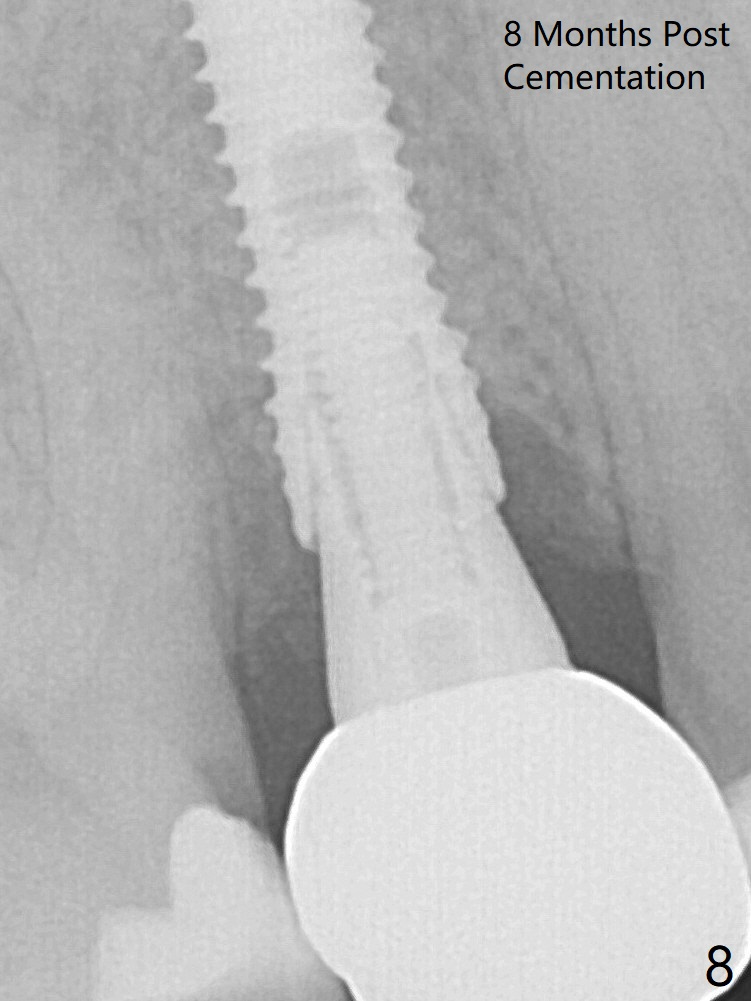

A 3.8x18 mm (definitive) implant is placed with <40 Ncm with the implant plateau apical to the lingual crest (Fig.4 (dashed line: upper border of the buccal defect)).  The buccal plate defect is repaired by Vanilla Graft (Fig.6 *) before and after insertion of a 4.5x4(3) mm abutment.  The buccal plate defect seems to being repaired 4 months postop (Fig.7).  The defect repair is close to completion 8 months post cementation (Fig.8).